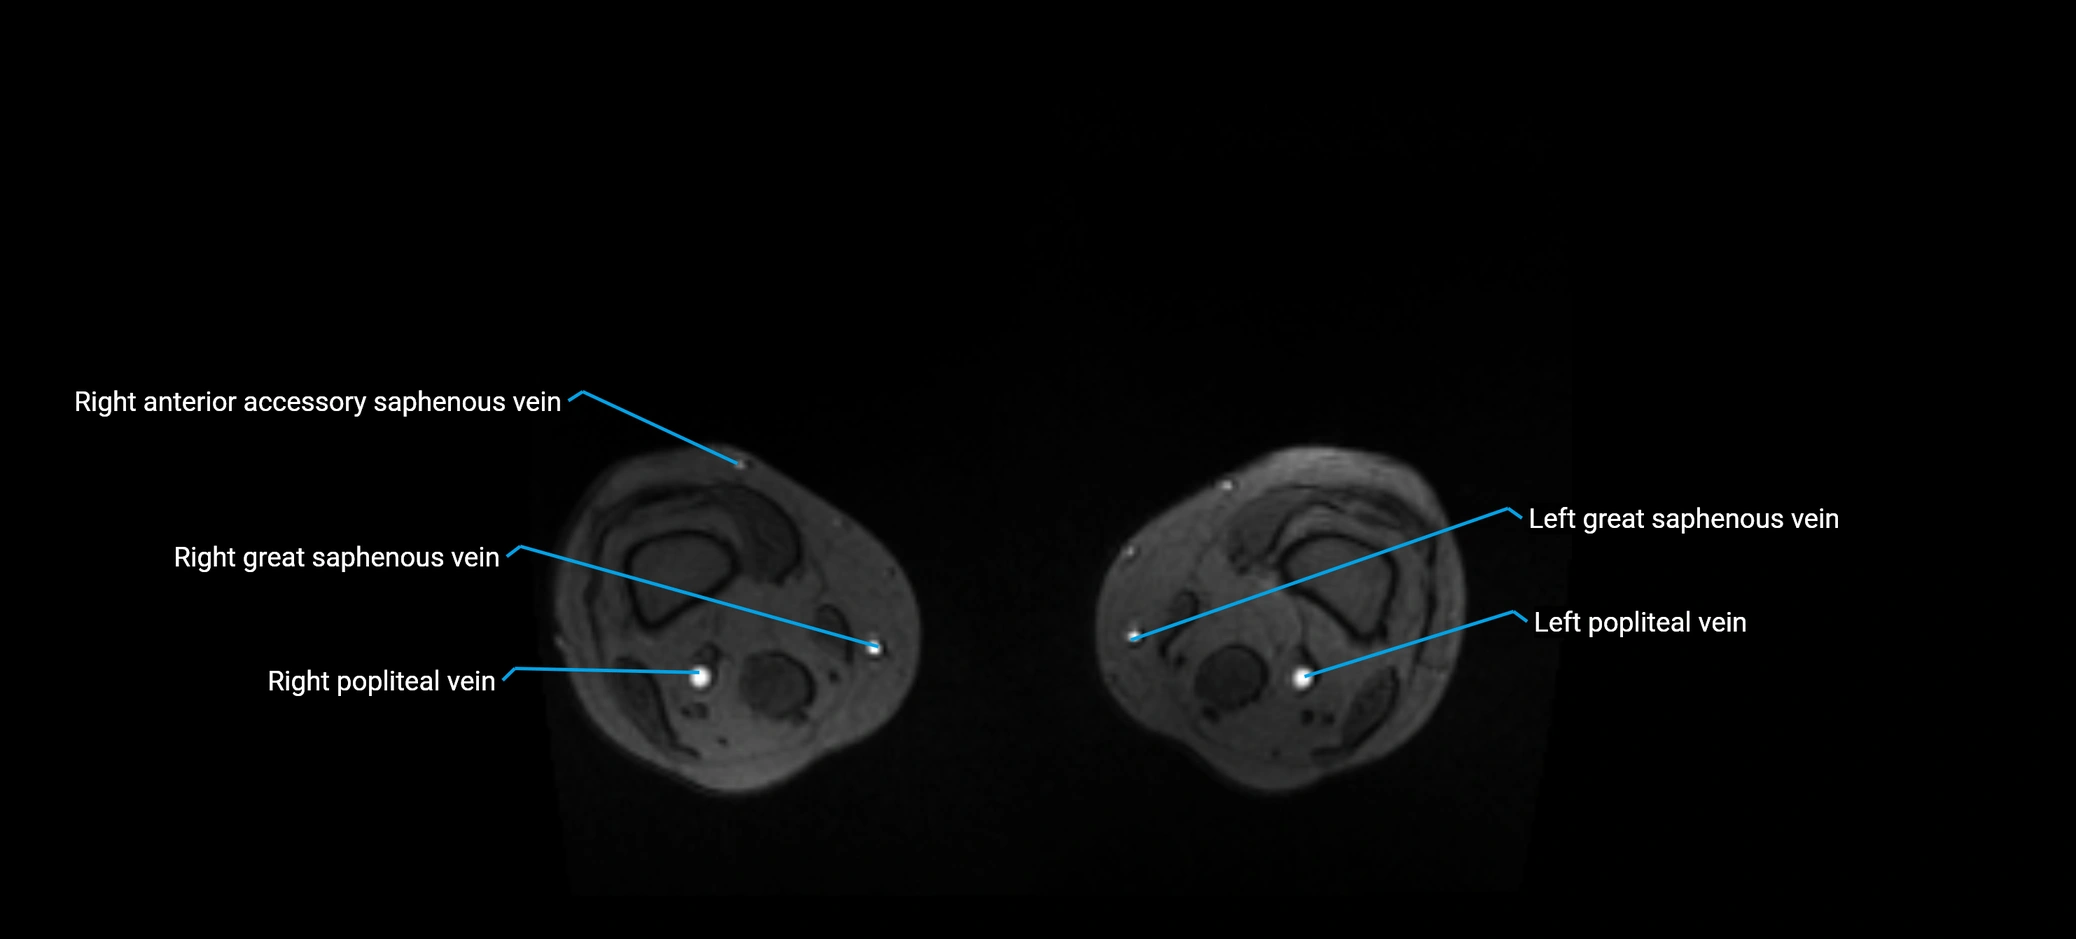

MRI image

image